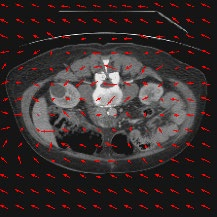

Transformers have made remarkable progress towards modeling long-range dependencies within the medical image analysis domain. However, current transformer-based models suffer from several disadvantages: (1) existing methods fail to capture the important features of the images due to the naive tokenization scheme; (2) the models suffer from information loss because they only consider single-scale feature representations; and (3) the segmentation label maps generated by the models are not accurate enough without considering rich semantic contexts and anatomical textures. In this work, we present CASTformer, a novel type of generative adversarial transformers, for 2D medical image segmentation. First, we take advantage of the pyramid structure to construct multi-scale representations and handle multi-scale variations. We then design a novel class-aware transformer module to better learn the discriminative regions of objects with semantic structures. Lastly, we utilize an adversarial training strategy that boosts segmentation accuracy and correspondingly allows a transformer-based discriminator to capture high-level semantically correlated contents and low-level anatomical features. Our experiments demonstrate that CASTformer dramatically outperforms previous state-of-the-art transformer-based approaches on three benchmarks, obtaining 2.54%-5.88% absolute improvements in Dice over previous models. Further qualitative experiments provide a more detailed picture of the model's inner workings, shed light on the challenges in improved transparency, and demonstrate that transfer learning can greatly improve performance and reduce the size of medical image datasets in training, making CASTformer a strong starting point for downstream medical image analysis tasks.